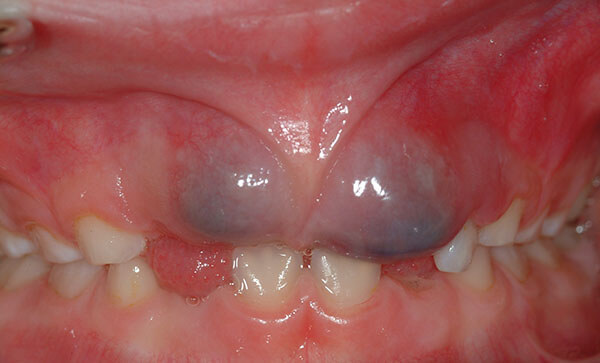

به طور کلی معمولا کیست ها فاقد علامت اند و درصورتی که پیشرفت کردن و بزرگ شدن فشار به بافت های حیاتی بدن مثل عصب ناحیه فک و صورت یا جابجایی دندان ها ویا تورم های فکی و لثه ای می توان آن را مشاهده کرد. اگر این کیست در سطح موکوزی دهان شما باشد، در ظاهر بیشتر شبیه تاول و یا زخم می شود و اگر هنوز عفونی نشده باشد، در بیشتر مواقع نشانه های واضحی وجود ندارد. در نتیجه در صورتی که کیست دندان شما تا حدی متورم شود که قابل دیدن و یا احساس کردن باشد، غیر قابل تشخیص است؛ مگر این که توسط دستگاه اسکن و یا دستگاه اشعه ایکس شناسایی شود.